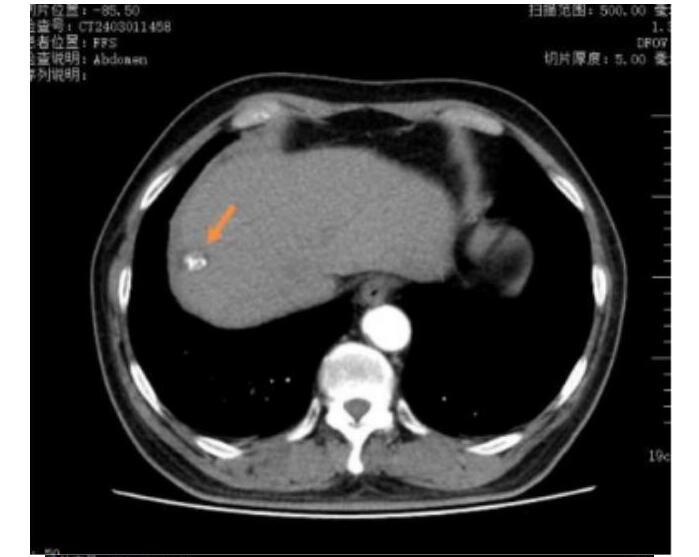

王先生(化名)65岁,2023年5月体检时发现肝占位,后行肝胆脾增强CT检查提示肝右叶富血供结节,径线约22mm*17mm,影像诊断考虑为肝恶性肿瘤,来到哈医大四院介入血管外科寻求进一步诊疗。患者行TACE术治疗后一周,接受了CT引导下冷冻消融治疗,术中患者疼痛轻微,术后患者恢复良好,三天后顺利出院。

术前上腹CT增强检查,考虑肝右叶恶性肿瘤

TACE联合冷冻消融